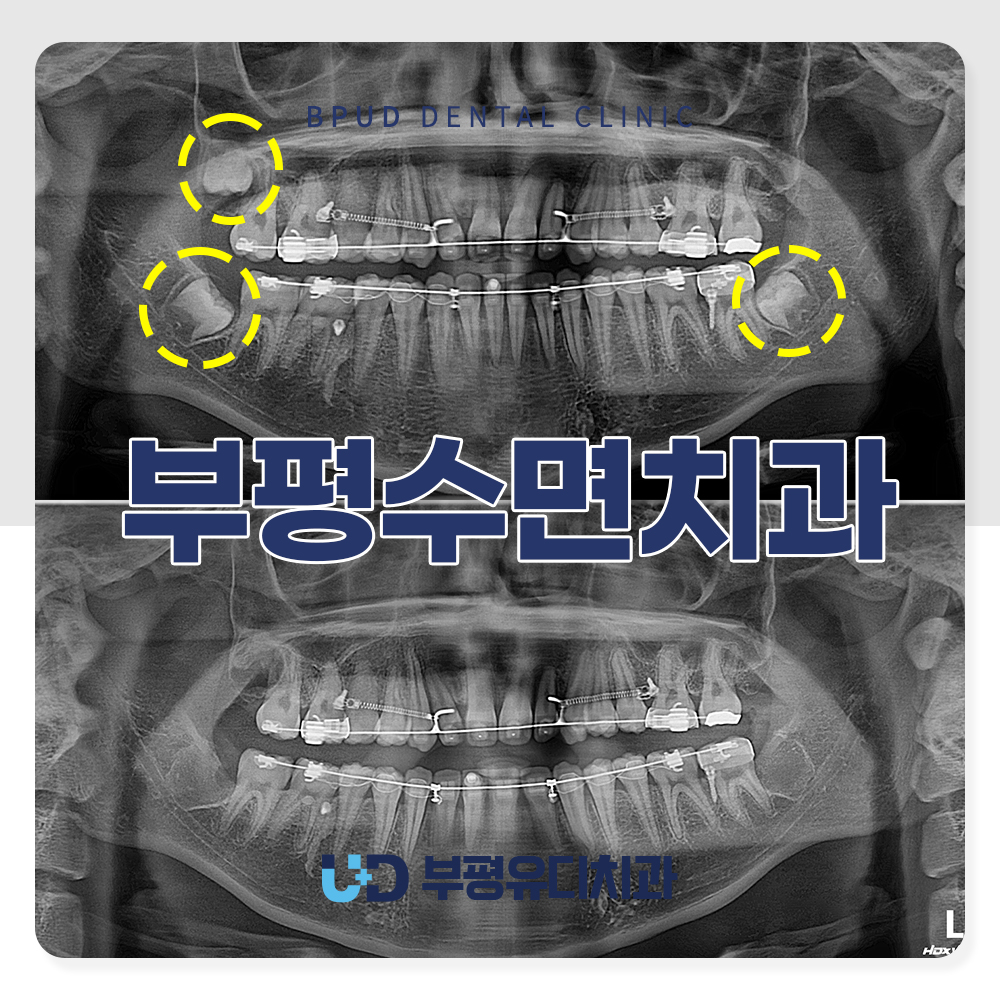

치아를 모두 발치한 후의 모습입니다.

매복 사랑니 발치는 국소 마취 후

잇몸을 절개하고 뼈를 일부 제거하여

사랑니를 노출시킨 뒤 치아를 분리하여

발치를 진행합니다.

어려운 케이스였지만 큰 문제없이

진행되었는데요.

완전 매복되어 있는 상태라 제거가

깔끔하게 되지 않을 시 잔류성 낭종이

생길 위험이 있는 치낭까지 완전히

제거를 하였습니다.